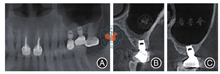

注:图7A为25、26戴入愈合基台后全景影像;图7B~ 7E分别为25、26戴入愈合基台后唇颊侧切面影像

注:图8A为戴牙后左侧上颌窦全景影像;图8B~ 8C分别为戴牙后25、26唇颊侧切面影像